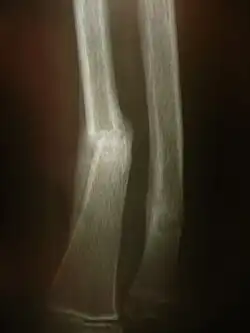

Radiographie montrant une fracture distale de l'avant bras.

Il s'agit des examens radiologiques utilisant la technologie radio la plus « basique ». Un tube à rayon X et une plaque radiologique. Le résultat de cet examen est une radiographie (d'un membre, pulmonaire, etc.).